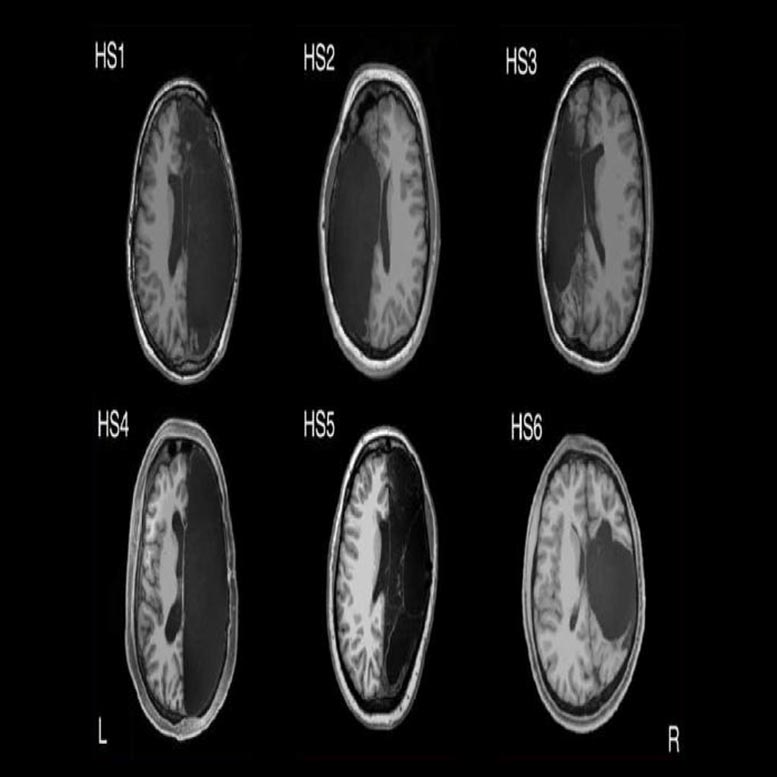

从顶部到大脑底部的结构磁共振图像(MRI,轴向取向)的视图,在患有癫痫患者的儿童时期的一个完整的半球。全局间歇性连接仍然是完整的,但随着网络之间的连接性增加,尽管有非典型脑解剖学,但是支持认知。

研究参与者,包括六名具有儿童半球切除术和六个控制的成年人,被指示放在FMRI机器中,放松,并尽量不要睡着,而研究人员在休息时追踪自发大脑活动。研究人员研究了已知的脑区网络,以控制视觉,运动,情感和认知等事物。他们还将在CALTECH脑成像中心收集的数据与脑基因组学超标项目的大约1,500个典型大脑的数据库进行了比较。

这张照片显示了一个FMRI扫描,从顶部到大脑底部的切片,由于癫痫,在儿童时期都有一个完整的半球。